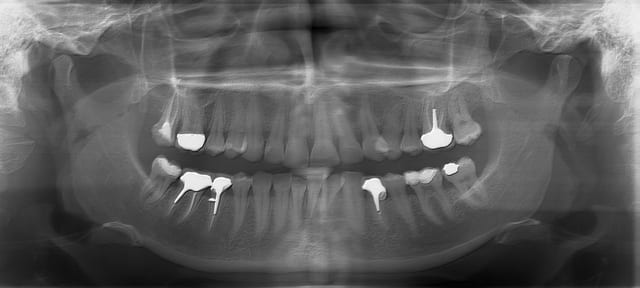

Sur 17, eMax CFAO sur silicone compatible (Heraeus Flexitime Fast and Scan) toujours avec G-Cem (pas eu le temps de passer les commandes), pas de digue (très vilain). Je n'ai pas fait l'endo dont l'oxyde de zinc en place depuis quelque temps a du colorer le collet.

Heureusement que c'est au fond je n'aime pas du tout l'aspect vestibulaire lié à l'économie tissulaire maximale, ça donne une impression de petite couronne anatomique comme sur une temporaire.

À refaire j'aurais abaissé la préparation en MV pour donner au joint l'impression qu'il limite collet et racine.